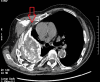

Empyema necessitans is a rare clinical finding nowadays. We report the case of a patient admitted in our ward for investigation of an unknown onset anterior chest wall mass, with no accompanying signs or symptoms. It is noteworthy that the patient had had pulmonary tuberculosis submitted to thoracoplasty more than 60 years before. Thoracic MRI showed a large heterogeneous mass, with a thick wall and internal septations located at the right anterior chest wall, as well as a heterogeneous content inside the right pleural cavity, with direct communication between both. An aspirative puncture of both masses was performed, with positive cultures for Mycobacterium tuberculosis, thus leading to the diagnosis of pleural tuberculosis with anterior chest wall empyema necessitans. A drain was inserted and antibiotics started. This case draws our attention to a very rare complication of pulmonary tuberculosis and its surgical treatment, though it aroused many decades after primary infection.